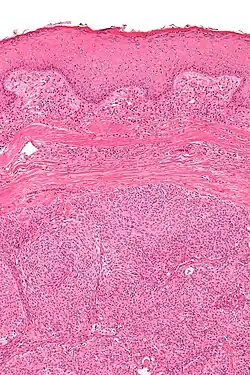

Micrograph showing an acrospiroma. H&E stain.

Hidradenoma refers to a benign adnexal tumor of the apical sweat gland.[1][2] These are 1–3 cm translucent blue cystic nodules. It usually presents as a single, small skin-colored lesion, and may be considered closely related to or a variant of poromas.[3] Hidradenomas are often sub-classified based on subtle histologic differences, for example:[4]